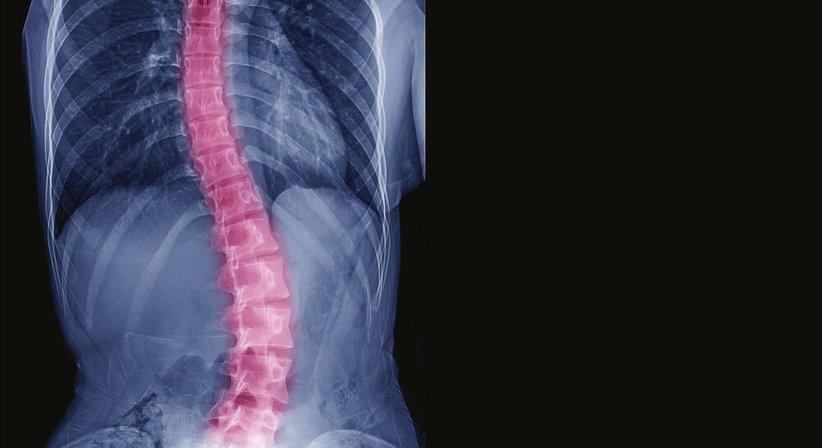

Bei einer Skoliose handelt es sich um eine Seitenabweichung der Wirbelsäule von der Längsachse, meist mit einer Rotation der Wirbelkörper – die Wirbelsäule wächst sozusagen in eine fehlerhafte Verdrehung hinein bzw. verkrümmt sich zur Seite.

Erkennen lassen kann sich eine Skoliose beispielsweise daran, dass die Schultern unterschiedlich hoch stehen, die Rippen und das Schulterblatt auf einer Seite stärker zu sehen sind und sich auf der anderen Seite im Bereich der Flanke eine Erhebung bildet (Schulterschiefstand, “Rippenbuckel“). Diese kosmetischen Auffälligkeiten können belastend sein, vor allem auch für Kinder und Jugendliche.

Die Therapie beruht auf einer umfassenden Abklärung und exakten Diagnose und wird für jeden Patienten entsprechend der individuellen Umstände und Bedürfnisse individuell erarbeitet.Eine besonders wichtige Rolle für die Behandlungsplanung spielen, neben anderen Faktoren, der Schweregrad der Skoliose (u. a. ermittelt anhand des COBB-Winkels, welcher auf den Röntgenbildern für die Abschnitte der verdrehten Wirbelsäule ausgemessen wird), die Skolioseform, das Krümmungsmuster, das Alter und die körperliche Verfassung.